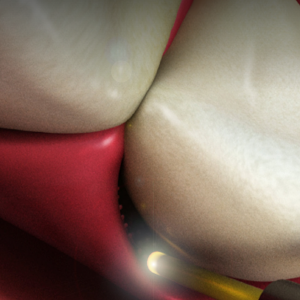

Early Caries Detection: The Key to Tooth Longevity

Tuesday, March 21, 2017

Early detection of caries can have life-long benefits for your patients, but radiographs have limitations when it comes to interproximal decay. Now, NIR Transillumination technology offers a highly accurate diagnostic alternative that supports minimal intervention dentistry.